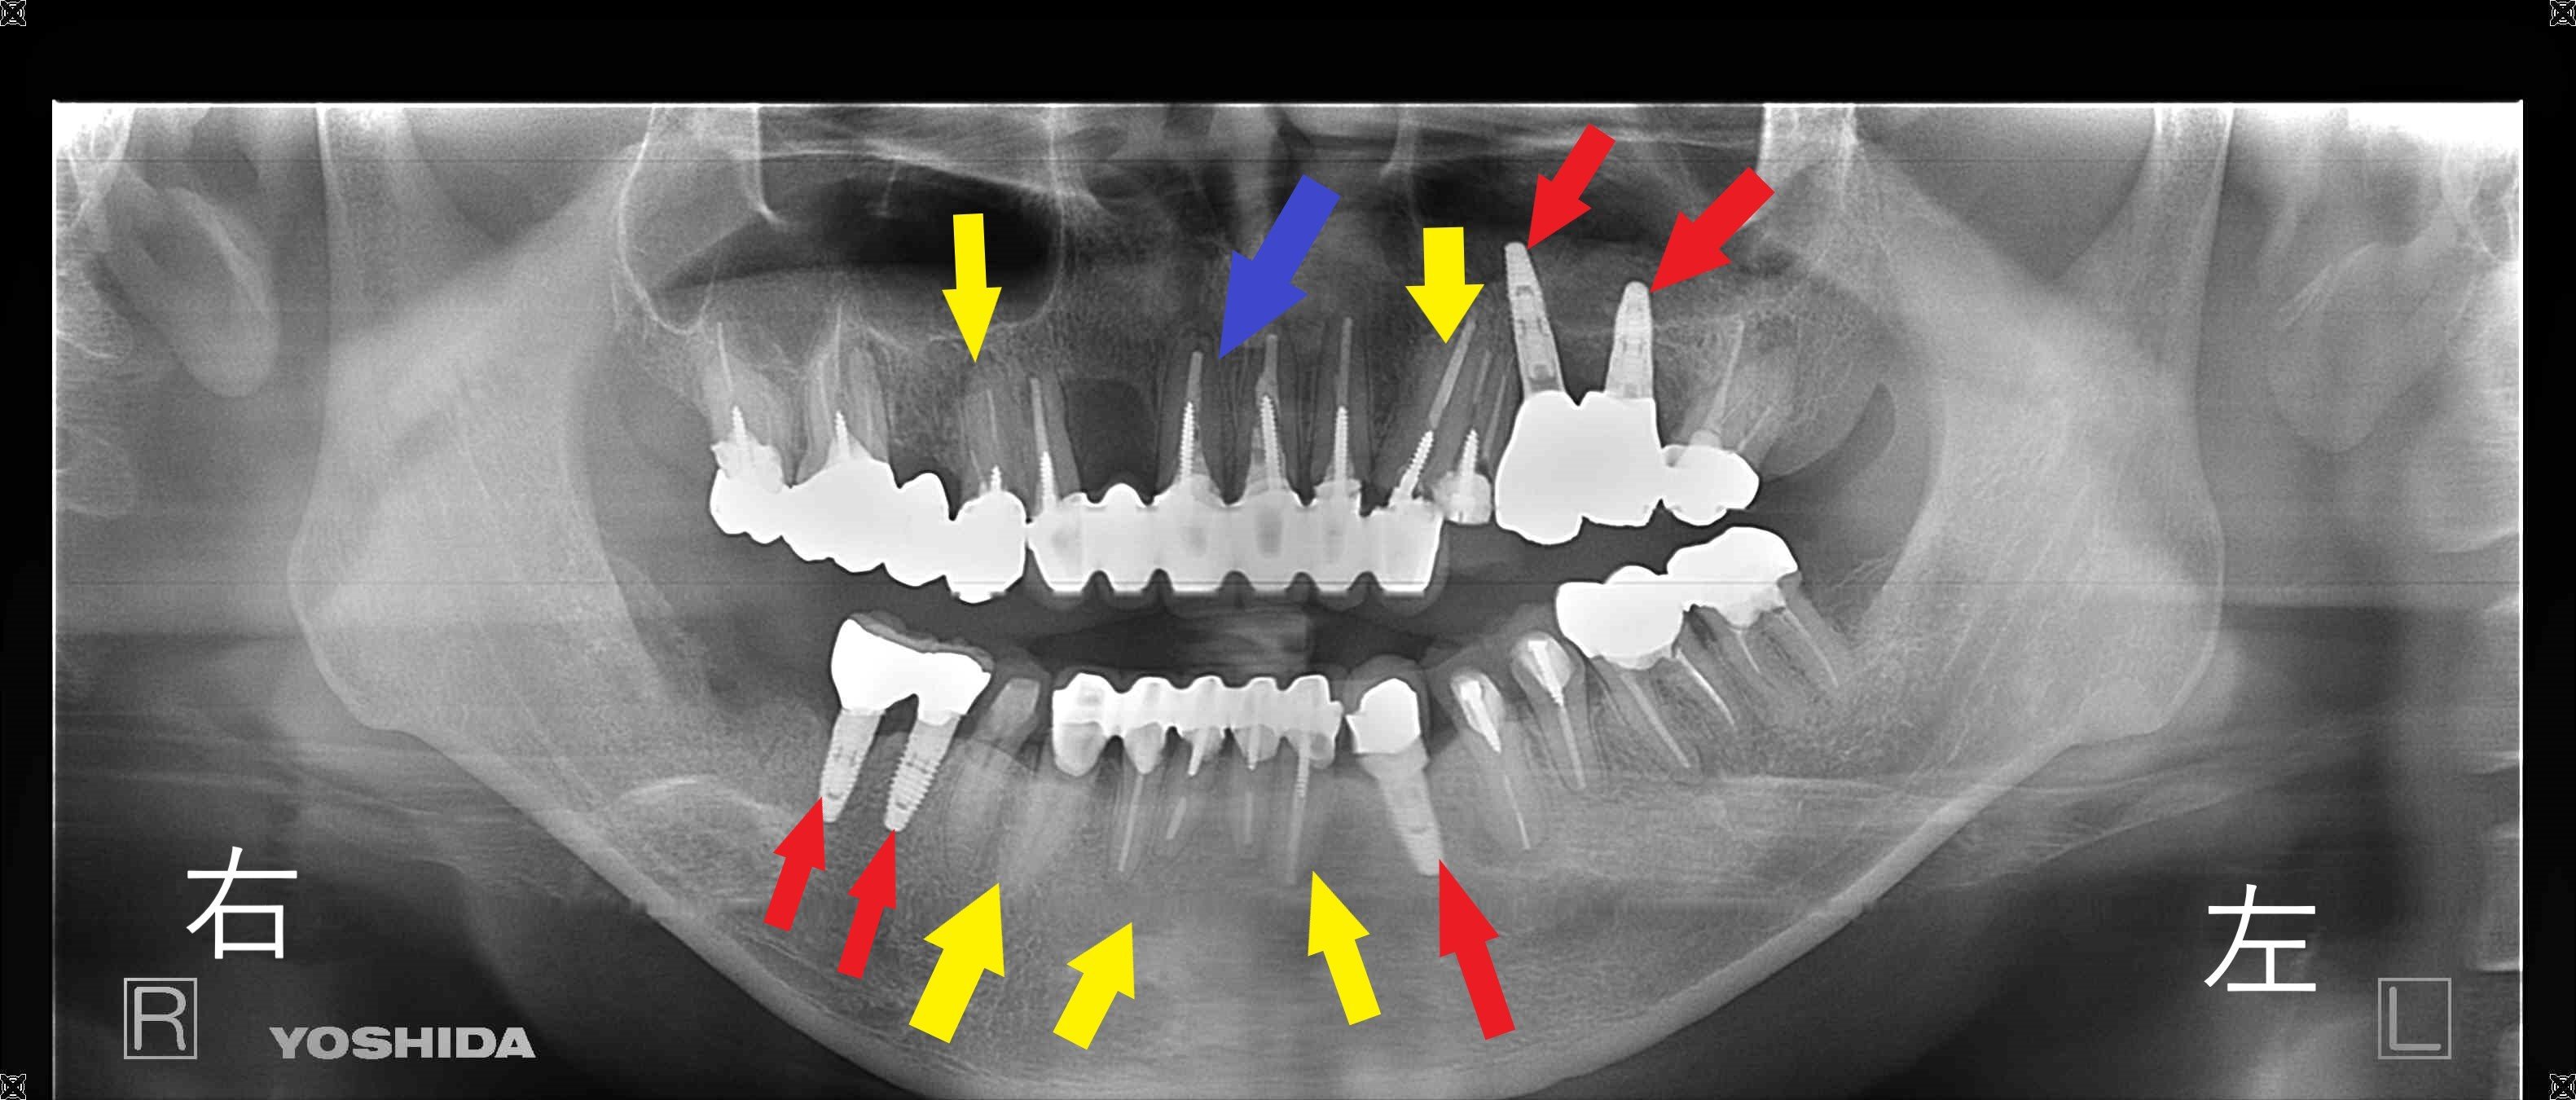

《レントゲン所見》

パノラマレントゲン画像では、虫歯による重度の歯質欠損や残根状態が複数部位に確認されました(黄色矢印部位)。

赤色矢印の部位は残念ながら抜歯せざるを得なかったところにインプラントを埋入した歯です。